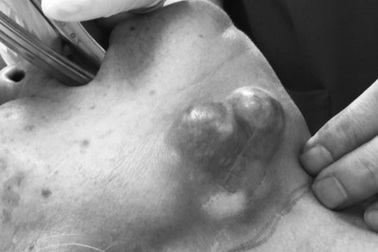

Dấu hiệu cảnh báo ung thư tuyến nước bọtUng thư tuyến nước bọt là một bệnh ung thư hiếm gặp, ảnh hưởng đến bất kỳ tuyến nước bọt nào trong số ba tuyến nước bọt chính: tuyến mang tai, tuyến dưới hàm và tuyến dưới lưỡi.

Nhận biết ung thư tuyến nước bọt giai đoạn sớmUng thư tuyến nước bọt xuất hiện ở mọi lứa tuổi và ảnh hưởng rất lớn đến sức khỏe con người.